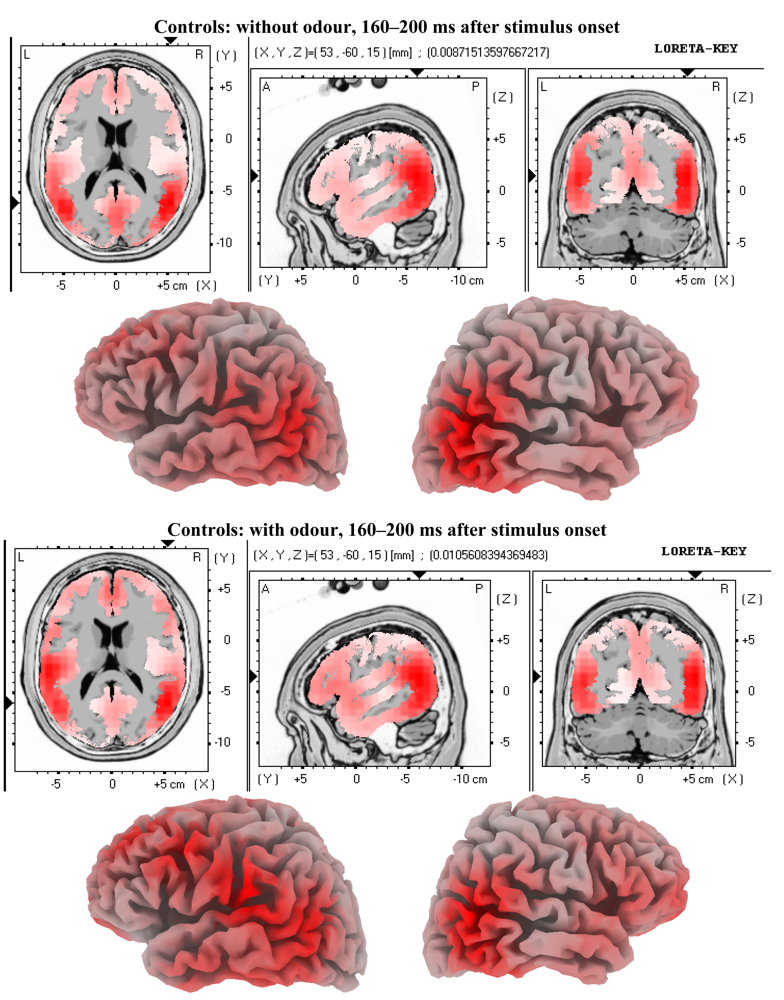

3.2. EEG Data